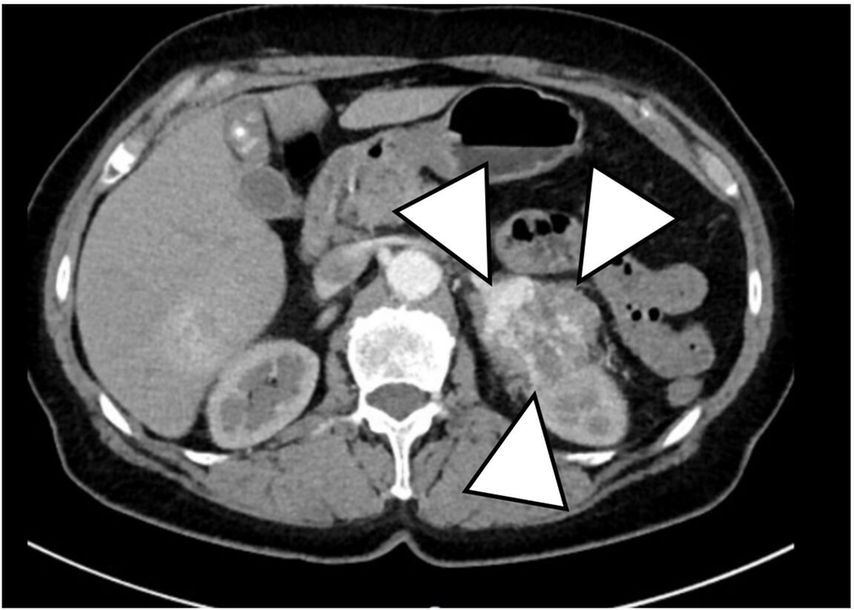

Nach Bestätigung der CS-Diagnose erfolgen weitere Tests zur Lokalisationsdiagnostik. Bei massiver Hypercortisolämie wird umgehend eine Computertomografie von Thorax und Abdomen empfohlen (Abb. 1). Plasma-ACTH-Konzentrationen helfen zur biochemischen Differenzialdiagnose zwischen ACTH-abhängigem und -unabhängigem CS. Für die Lokalisationsdiagnostik des ACTH-abhängigen CS werden ein CRH-Test, ein Langzeit-Dexamethason-Hemmtest sowie eine Hypophysen-MRT benötigt (Abb. 2). Ein Hypophysenadenom ist als Zufallsbefund bei bis zu 10% der Bevölkerung zu erwarten, andererseits lässt sich nur bei 60% der Patienten mit hypophysärem CS ein Hypophysenadenom lokalisieren. In unklaren Fällen wird eine Sinus-petrosus-inferior-Katheterisierung für die Lokalisationsdiagnostik benötigt.5

Abb. 1:CT Abdomen mit Nebennierenkarzinom (>5 cm) links